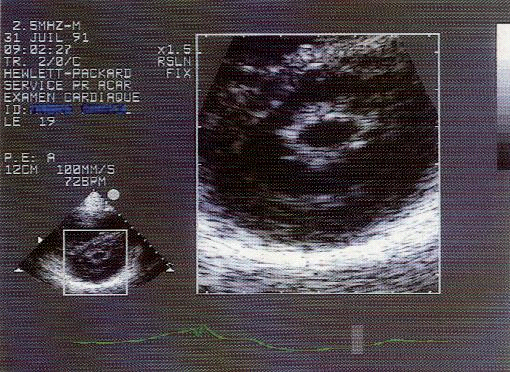

A. Siêu âm Doppler tim: là biện pháp thăm dò cực kỳ quan trọng để chẩn đoán xác định và chẩn đoán mức độ hẹp van hai lá, chẩn đoán hình thái van, tổ chức dới van hai lá và các thương tổn kèm theo (thường có trong HHL) giúp chỉ định điều trị.

1. Kiểu TM: lá van dày, giảm di động, biên độ mở van hai lá kém, hai lá van di động song song, dốc tâm trương EF giảm (EF dưới 15 mm/s là HHL khít).

2. Siêu âm 2D: hình ảnh van hai lá hạn chế di động, lá van hình vòm (hockey-stick sign), vôi hoá lá van và tổ chức dưới van. Siêu âm 2D còn cho phép đo trực tiếp diện tích lỗ van hai lá, đánh giá chức năng thất trái và các tổn thương van khác có thể kèm theo.